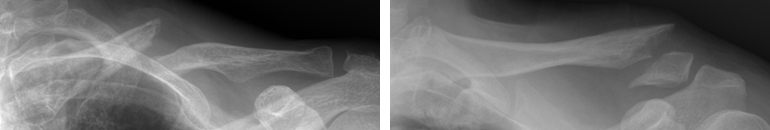

골절의 위치에 따라 내측, 중간, 외측 1/3로 나누며 중간부위 골절이 가장 흔합니다.

우측 쇄골의 중간(좌), 원위부(우)가 골절되어 어긋나 있습니다. 우측 쇄골의 중간(좌), 원위부(우)가 골절되어 어긋나 있습니다.